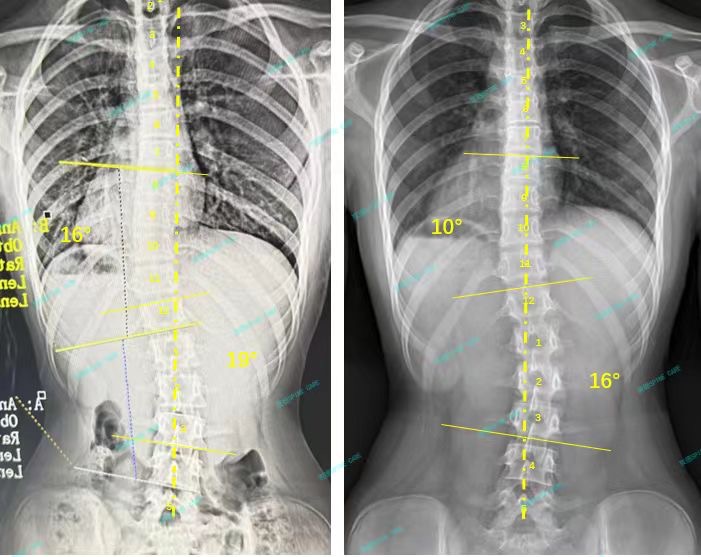

三个月训练后的x片显示我的胸弯从16度降到了10度,腰弯从19度降到了16度,身体看起来也比以前直了,我和爸爸妈妈都很开心,我还会继续坚持在这里训练,直到完全恢复正常。

X-rays after three months of training showed that my chest bend had dropped from 16 degrees to 10 degrees, my waist bend had dropped from 19 degrees to 16 degrees, and my body looked straighter than before. My parents and I were very happy. I will continue to train here until I fully return to normal.